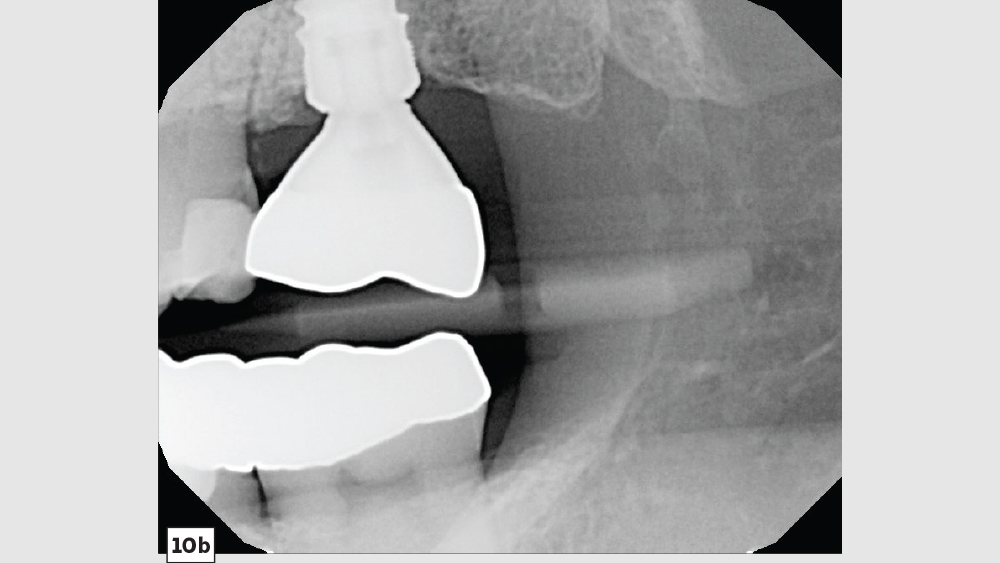

A patient presented with issues concerning a screw-retained crown in the area of tooth #15. She complained that the crown felt loose, was causing food entrapment and was difficult to clean. Upon examination, it appeared that the prosthetic screw was loose and the restoration was mobile. Removal of the crown confirmed that the current design of the prosthesis created a food trap and was not conducive to soft-tissue health. We agreed that the restoration needed to be replaced. A screwmentable restoration was the optimal solution because the malposition of the implant could be corrected by a custom abutment, thereby minimizing the cantilever. We wanted to improve the direction of loading and lessen sheer forces on the implant site by building the restoration out with the titanium structure of the custom abutment. At the same time, because the implant site was in a hard-to-reach area from which cement removal would have been difficult, screw retention was preferred.